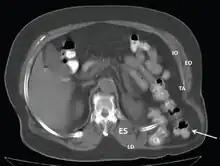

CT scan-Grynfeltt-Lesshaft hernia.

Grynfeltt–Lesshaft hernia is a herniation of abdominal contents through the back, specifically through the superior lumbar triangle, which is defined by the quadratus lumborum muscle, twelfth rib, and internal oblique muscle.